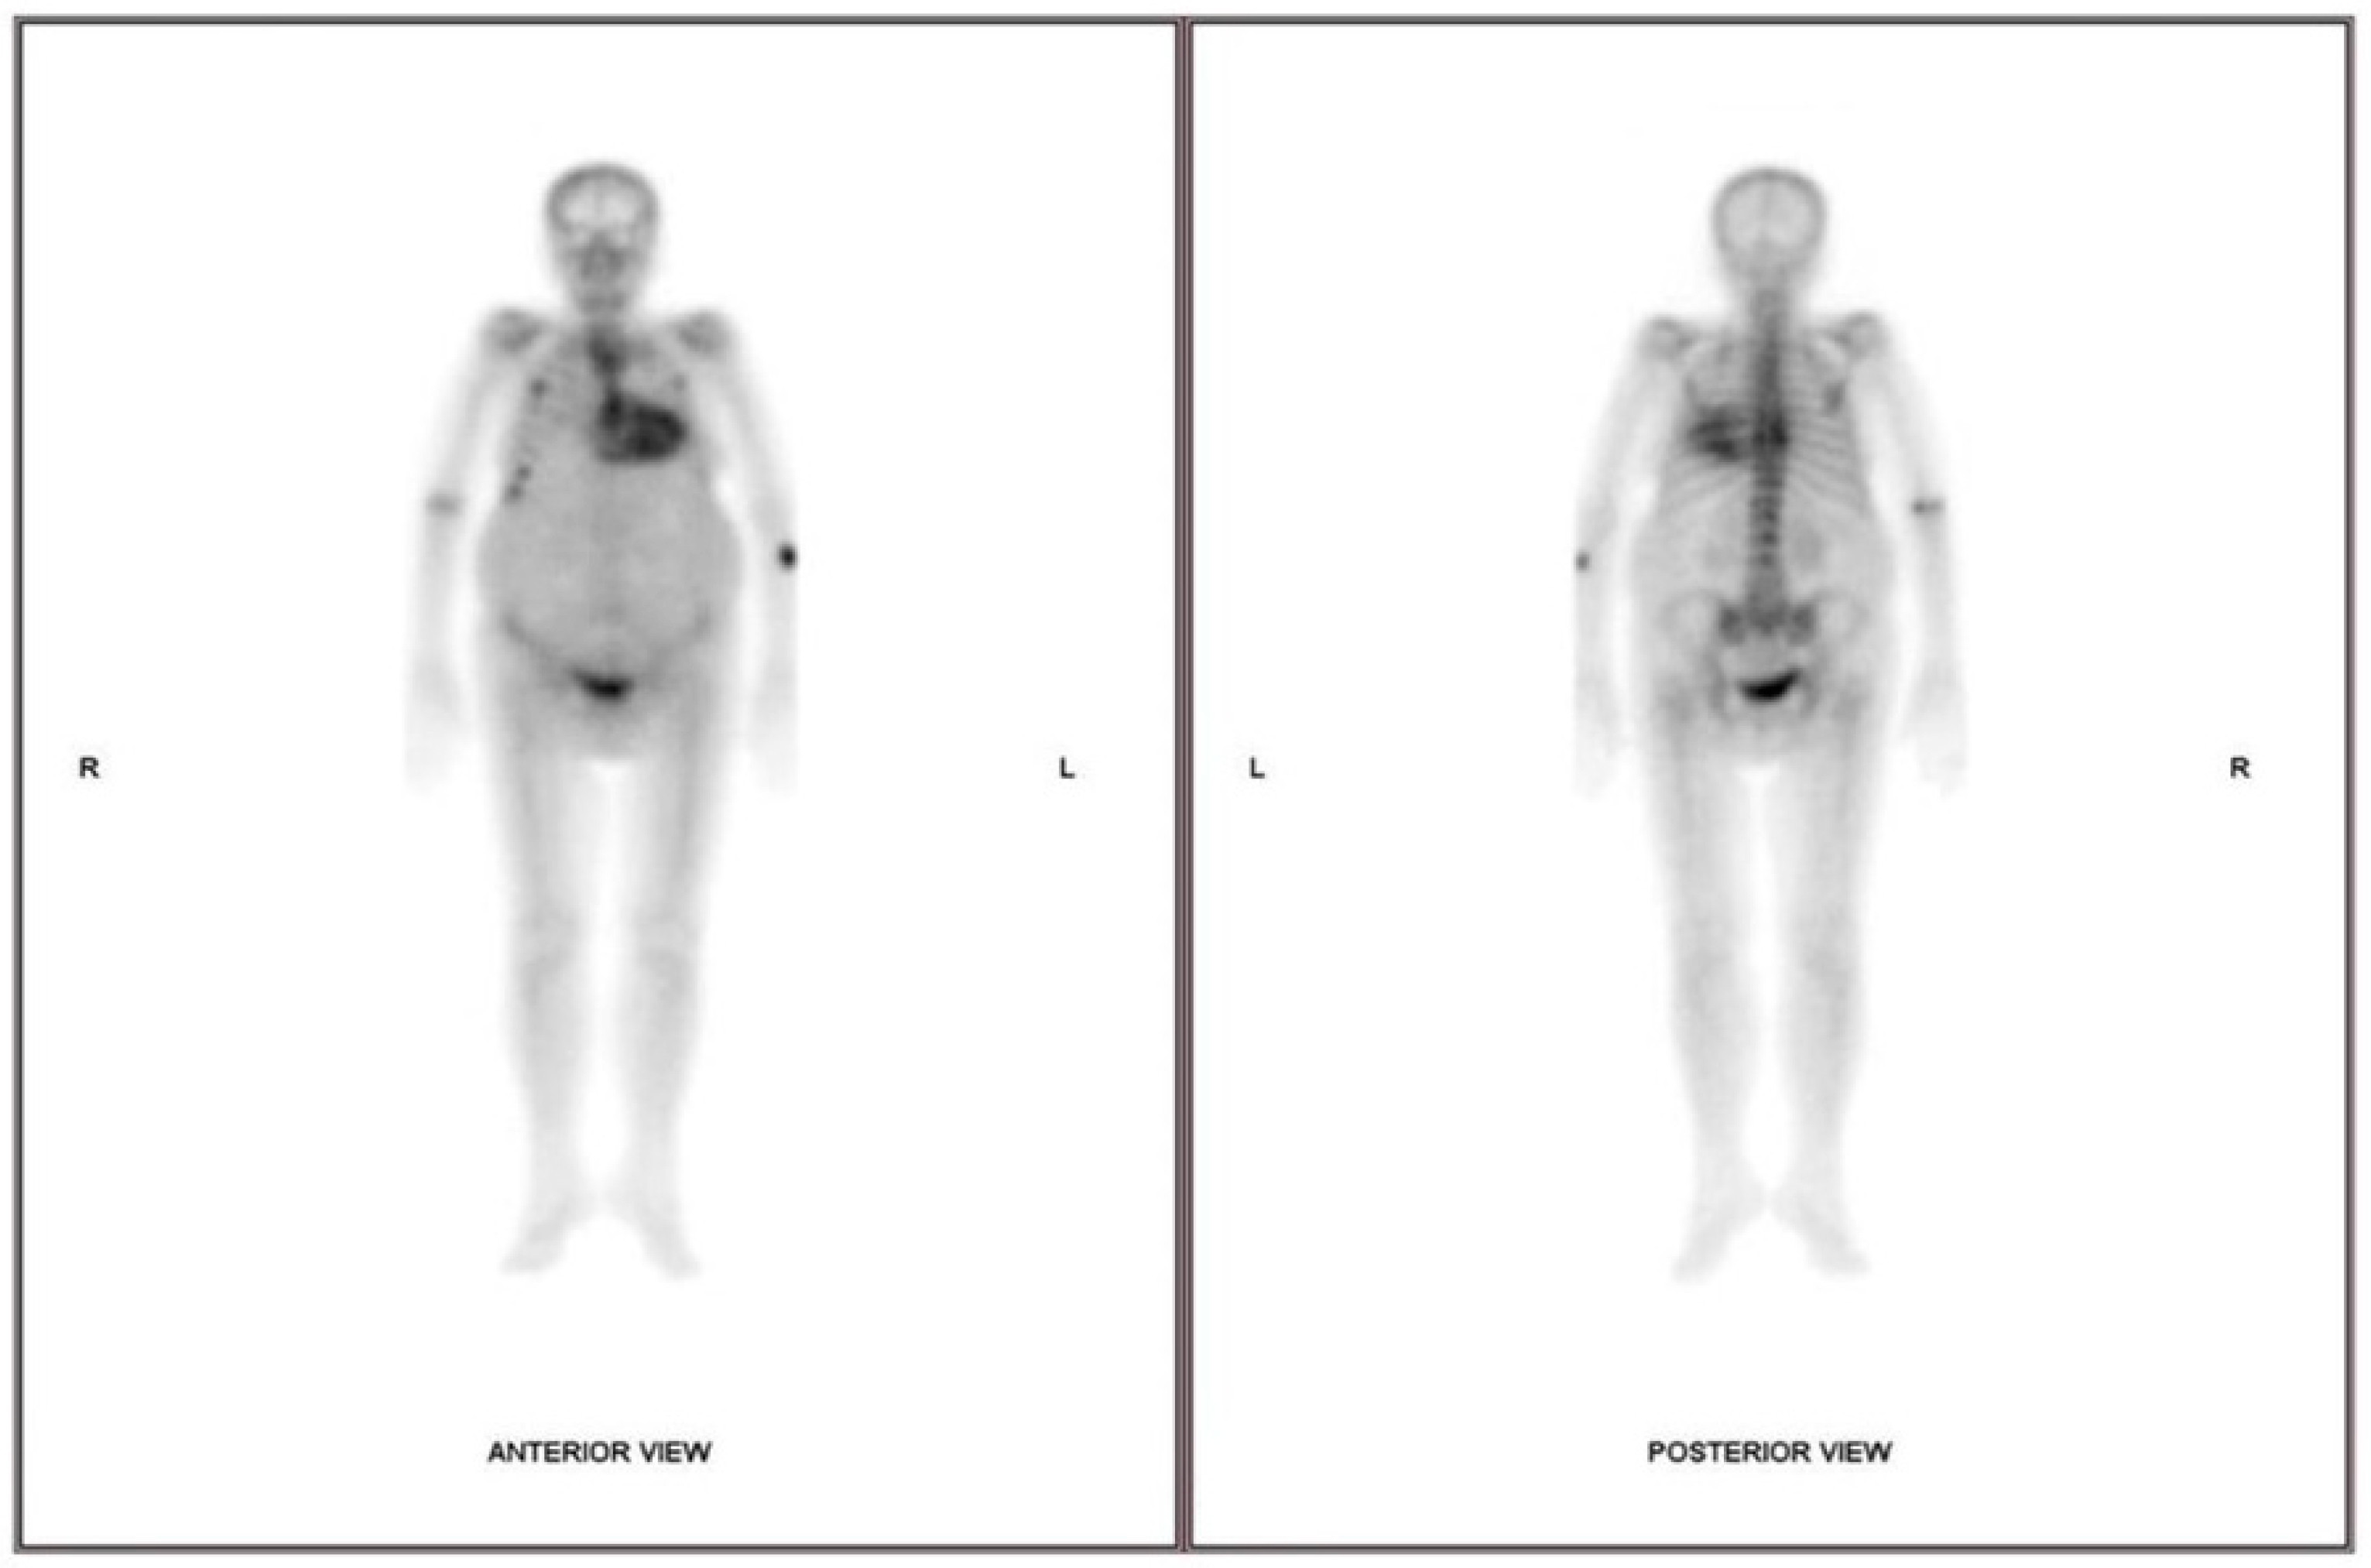

3.6. Cardiac Scintigraphy

- Perugini, E.; Guidalotti, P.L.; Salvi, F.; Cooke, R.M.; Pettinato, C.; Riva, L.; Leone, O.; Farsad, M.; Ciliberti, P.; Bacchi-Reggiani, L.; et al. Noninvasive etiologic diagnosis of cardiac amyloidosis using 99mTc-3,3-diphosphono-1,2-propanodicarboxylic acid scintigraphy. J. Am. Coll. Cardiol. 2005, 46, 1076–1084. [Google Scholar] [CrossRef]

- Dorbala, S.; Ando, Y.; Bokhari, S.; Dispenzieri, A.; Falk, R.H.; Ferrari, V.A.; Fontana, M.; Gheysens, O.; Gillmore, J.D.; Glaudemans, A.; et al. ASNC/AHA/ASE/EANM/HFSA/ISA/SCMR/SNMMI Expert Consensus Recommendations for Multimodality Imaging in Cardiac Amyloidosis: Part 1 of 2-Evidence Base and Standardized Methods of Imaging. Circ. Cardiovasc. Imaging 2021, 14, e000029. [Google Scholar] [CrossRef]

- Hanna, M.; Ruberg, F.L.; Maurer, M.S.; Dispenzieri, A.; Dorbala, S.; Falk, R.H.; Hoffman, J.; Jaber, W.; Soman, P.; Witteles, R.M.; et al. Cardiac Scintigraphy with Technetium-99m-Labeled Bone-Seeking Tracers for Suspected Amyloidosis: JACC Review Topic of the Week. J. Am. Coll. Cardiol. 2020, 75, 2851–2862. [Google Scholar] [CrossRef] [PubMed]

- Hutt, D.F.; Fontana, M.; Burniston, M.; Quigley, A.M.; Petrie, A.; Ross, J.C.; Page, J.; Martinez-Naharro, A.; Wechalekar, A.D.; Lachmann, H.J.; et al. Prognostic utility of the Perugini grading of 99mTc-DPD scintigraphy in transthyretin (ATTR) amyloidosis and its relationship with skeletal muscle and soft tissue amyloid. Eur. Heart J. Cardiovasc. Imaging 2017, 18, 1344–1350. [Google Scholar] [CrossRef]

- Ionescu, T.M.; Ciocoiu, M.; Lupusoru, R.V.; Grierosu, I.; Sascau, R.A.; Jalloul, W.; Iacob, R.; Stolniceanu, C.R.; Clement, A.; Statescu, A.M.; et al. Role of Diphosphonates Bone Scintigraphy in Correlation with Biomarkers for a Personalized Approach to ATTR Cardiac Amyloidosis in North-Eastern Romania. Diagnostics 2022, 13, 83. [Google Scholar] [CrossRef] [PubMed]